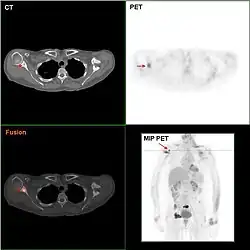

Die Positronen-Emissions-Tomographie ist derzeit keine Routinemethode, kann jedoch eingesetzt werden, um nach dem Primärtumor bzw. dessen Metastasen zu suchen, wenn dieser mit anderen Methoden nicht gefunden werden kann.

Knochenszintigramme, Computertomographien, Röntgenaufnahmen der Lunge, Sonographien der Leber und ggf. Kernspintomographien dienen dazu, nach Metastasen zu suchen, also die Ausbreitung der Erkrankung zu erkennen. Angesichts der Tatsache, dass die PET/CT bis auf die MRT-Hirn- und Brustuntersuchung genauer ist und zugleich auch andere Krebserkrankungen ausschließen kann, erscheint die PET/CT sinnvoller als Knochenszintigramme, Computertomographien, Röntgenaufnahmen der Lunge und Sonographien der Leber zusammen.